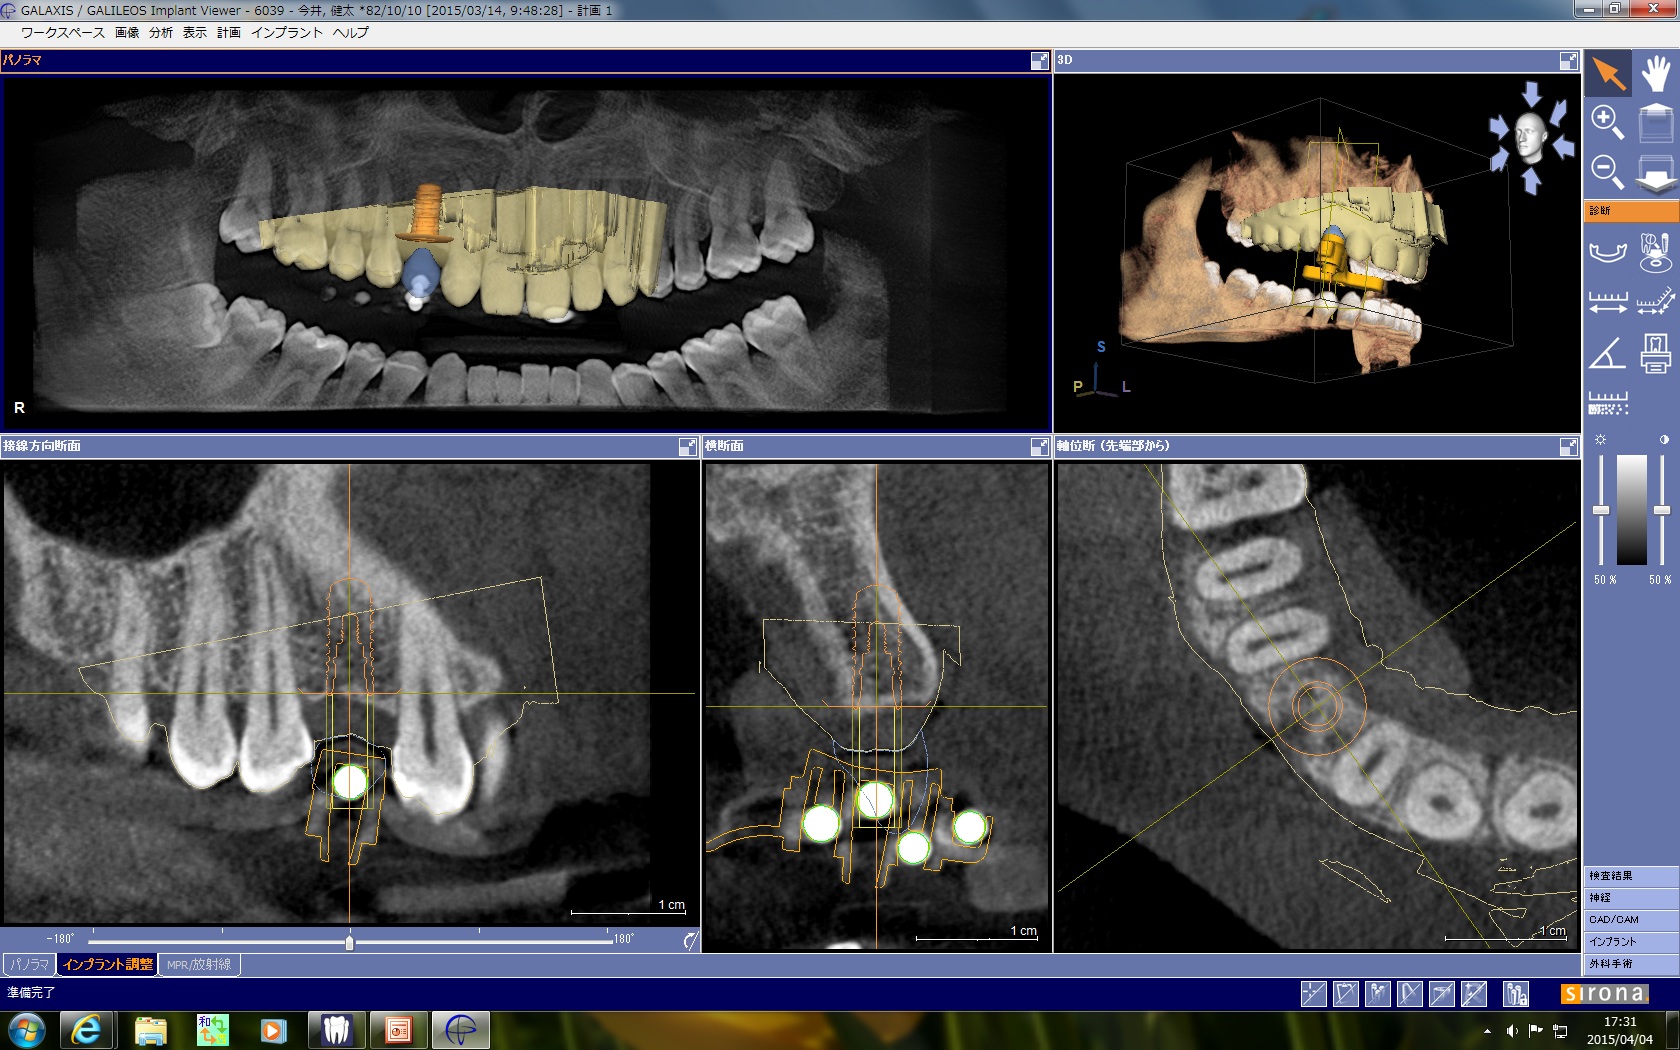

今日は、先天性欠損の右上犬歯部位にガイドサージェリーで、ストローマンボーンレベルインプラントのRC 4.1Φ10mmを埋入しました。

口蓋側の基底結節部にアクセスホールが来るように、埋入角度とポジションを正確に口腔内に埋入するために、セレックガイドを使用しました。

歯冠形態をデジタルワックスアップで行い、画像をプランニングソフトのCT上にインポートしてガイドの作成を行います。

術前のプランニングソフトでインプラントの埋入の位置、角度、深さを3次元的に計画します。